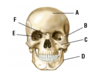

What is the most common type of joint between the bones of the skull?

Suture joint (fibrous)

What are the 3 parts that the skull can be divided into?

Neuro-cranium

Facial skull (viscera-cranium)

Mandible

What part of the skull is A?

Neuro-cranium

What part of the skull is B?

Facial skull (viscera-cranium)

What part of the skull is C?

Mandible

What is A?

Frontal bone